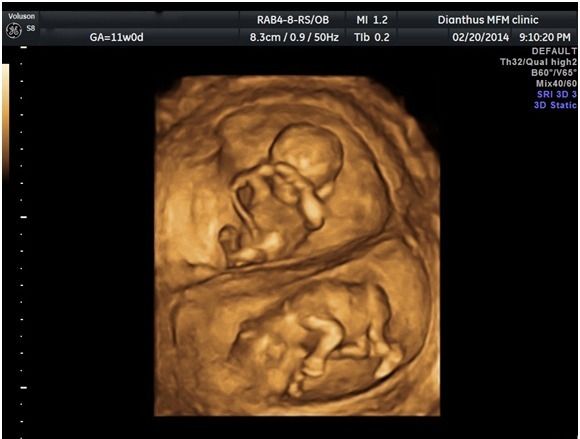

至於進一步來談談3D/4D超音波,3D超音波就是立體超音波,利用影像資料重組出寶寶的外觀,就和照相一樣,而4D超音波則是再加上動態的錄影,一般的3D/4D並不具診斷的功能,而是一種讓準爸媽提早與寶寶見面的立體動態影像工具。

所以,有醫師會說,傳統二維超音波就足夠做診斷的用途了,3D/4D只有娛樂價值、噱頭啦。其實沒什麼好爭辯的,基本上,我對於要不要做也沒什麼特別看法。只是,我本就是大嘴巴,所以還是多嘴補充一下,能做3D/4D 的超音波,一定都是高階等級儀器,因為畢竟要重組影像一定要有優良的二維影像解析能力,所以如果大家搞不清楚醫療院所超音波儀器之好壞,這就是一個最簡單的判斷方式了。畢竟二維影像的解析度,就大大關係著診斷之品質嘍。(嗯,我會不會透露太多了,呵呵。)